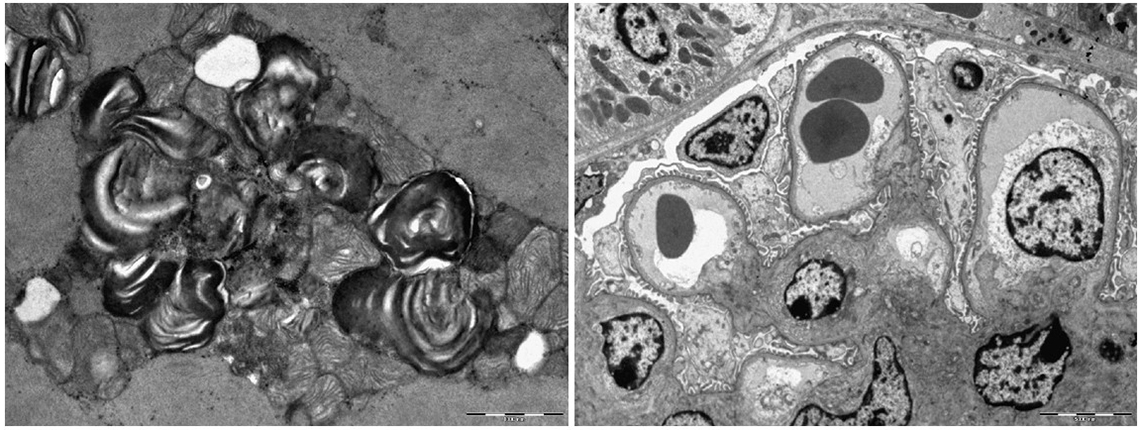

Laboratorio di ricerca su tematiche inerenti terapie oncologiche a bersaglio molecolare utilizzando modelli cellulari 2D e 3D.

Analisi morfologica microscopica ed ultrastrutturale di patologie umane.